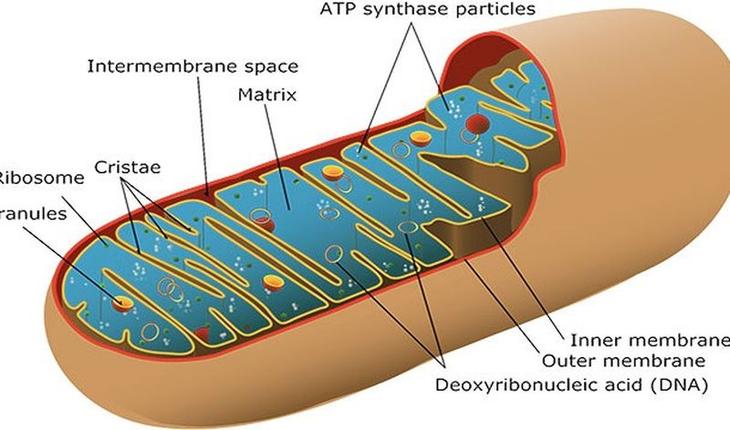

3) Митохондриальные заболевания передаются ребенку исключительно от матери и никогда – от отца.